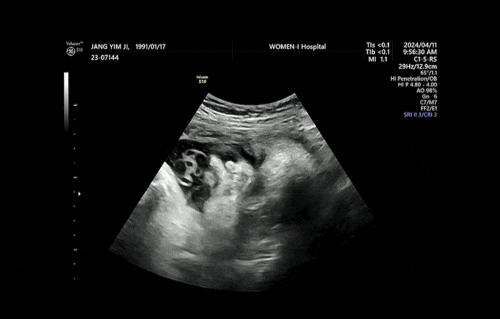

임신기록/37주차 증상 및 초음파 , 출산 전 마지막 진료

37주차 증상 및 기록 - 36주차 증상과 동일 - 병원서 제왕절개 수술 동의서 작성 - 수술에 관한 설명 듣고 ...